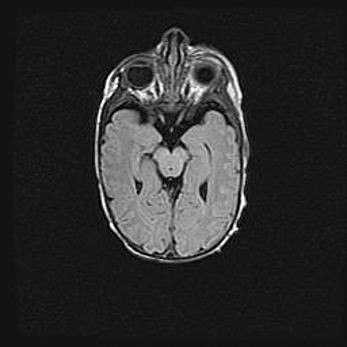

Сообщающаяся гидроцефалия. Кистозная энцефаломаляция головного мозга.

Возраст: 3 месяца 4 дня

Вес: 3100 г

Пол: женский

Окружность головы: 34 см

Срок гестации: 31 неделя

Кистозная энцефаломаляция головного мозга - одна из форм поражения головного мозга в детском возрасте. Характеризуется возникновением множественных и распространённых кист в коре, белом веществе и подкорковых образованиях головного мозга у плодов, новорождённых и детей раннего возраста. Развитие кистозной энцефаломаляции связано с внутриутробной асфиксией и гипотонией, родовой травмой, тромбозом синусов, пороками развития сосудов, инфекциями, сепсисом и другими причинами. Наиболее значимые инфекционные агенты: вирусы простого герпеса, цитомегалии, краснухи, токсоплазмы, энтеробактерии, золотистый стафилококк и другие.